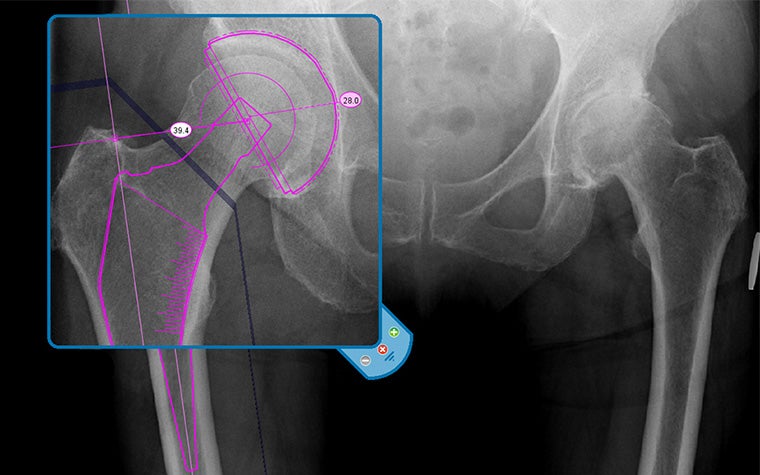

Join this training course for a quick start in digital templating using one of the most trusted planning tools in the market, Materialise OrthoView, which has a 96% planning accuracy in THA. You'll learn how to perform the most optimal workflows for planning total hip replacement and total knee replacement procedures.

- How to scale X-ray images, analyze biomechanics, and template for knee and hip replacement

It will give you the foundation to learn templating using X-ray scaling, analysis tools, and smart templates.